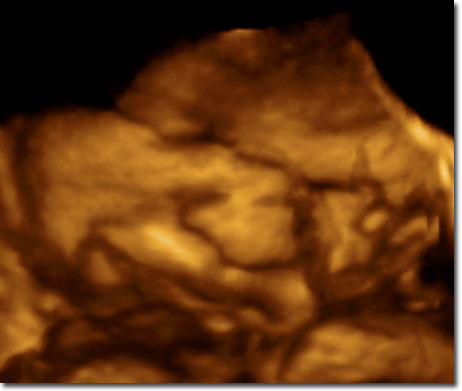

Live 3/4 D Ultraschall

12. SSW

30.

SSW

35. SSW

Baby

vor der Geburt im 3D Ultraschall und gleiches Baby nach der Geburt!